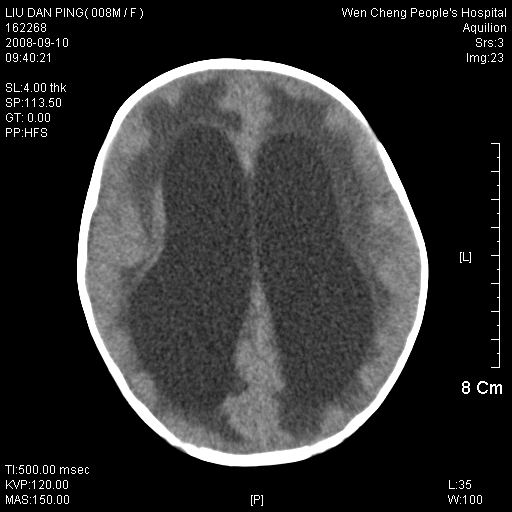

以下是引用卜一在2008-9-10 16:21:00的发言:[br]髓母细胞瘤伴梗阻性脑积水!支持![br]髓母细胞瘤特点:—般直径大于3.5cm,位于后颅凹中线之小脑蚓部。累及上蚓部的肿瘤延伸到小脑幕切迹之上,ct平扫肿瘤多呈均匀一致的高或等密度病灶,增强检查呈均匀一致的强化。病灶中有小坏死时,平扫亦可呈不均匀之混杂密度,注药后有增强。[br]

以下是引用zjzjr在2008-9-10 15:09:00的发言:[br]髓母细胞瘤伴梗阻性脑积水.